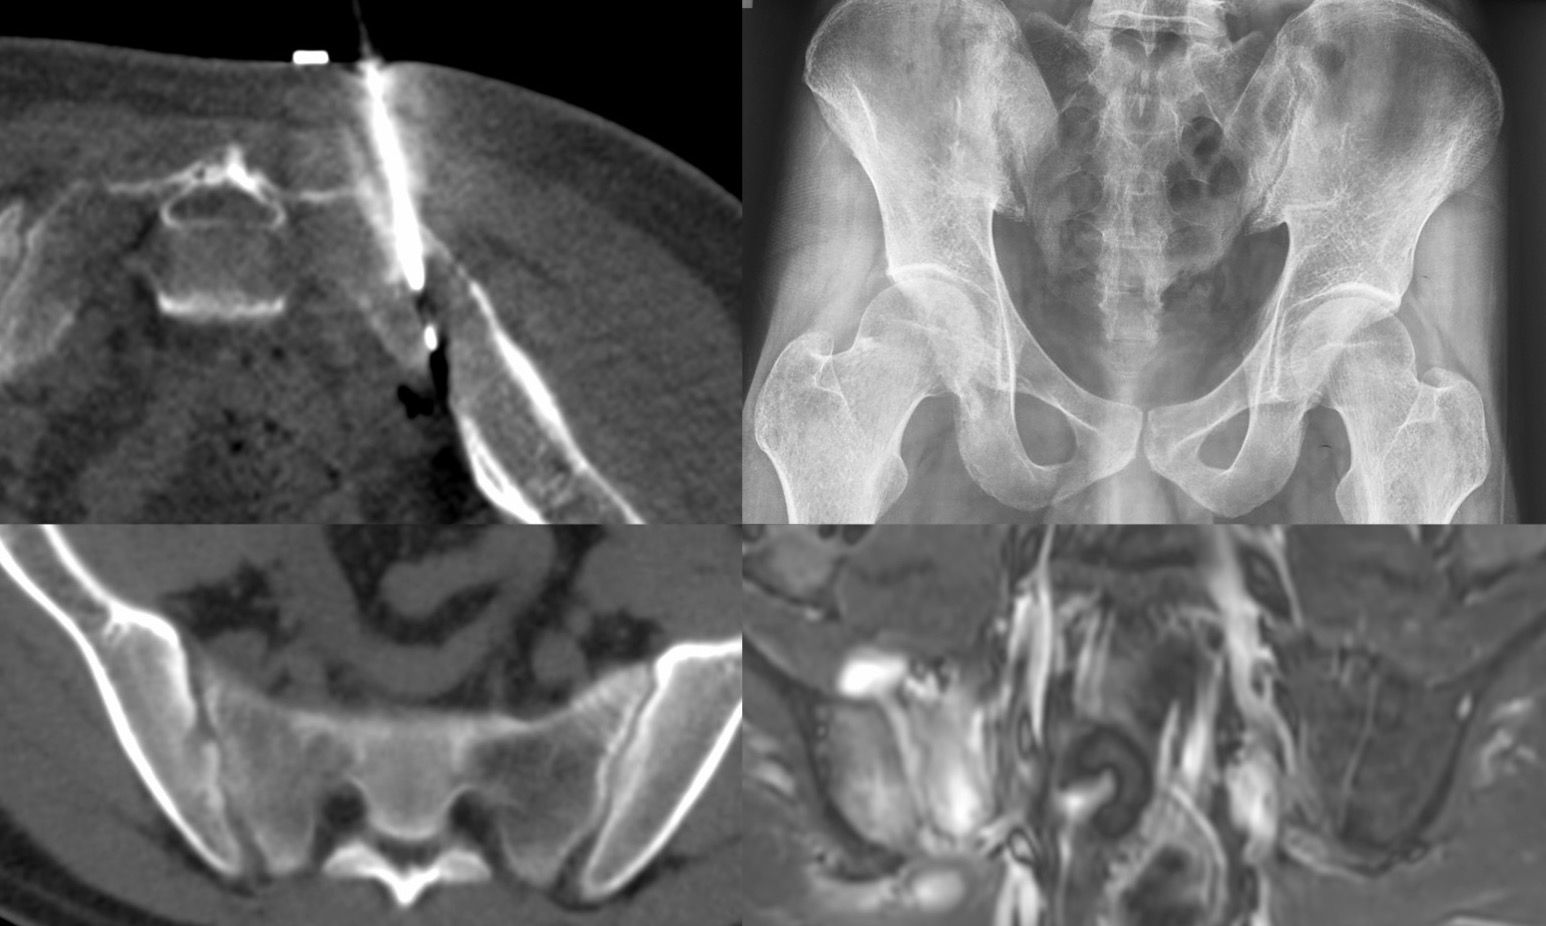

Case 61: Sacroiliac Joint Biopsy in Mild to Moderate Sacroilitis

Bhavin Jankharia - 01 October 2021

Case 60: Sacroiliac Joint Biopsy

Bhavin Jankharia - 24 September 2021